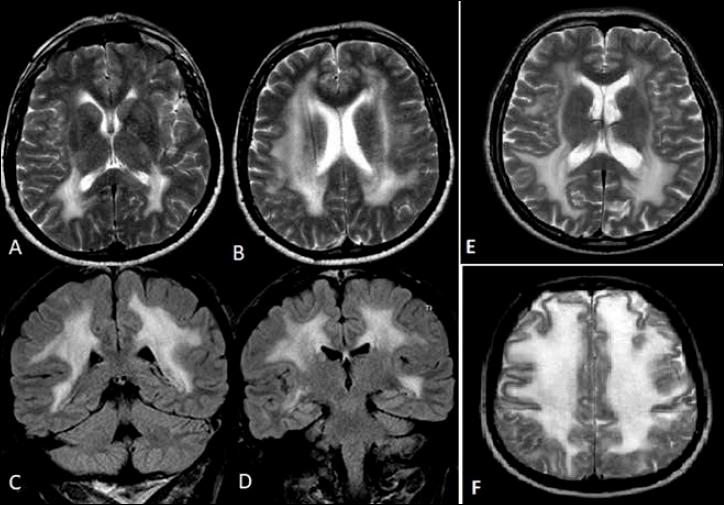

Mutations in gene, encoding merosin, are generally responsible of a severe congenital-onset muscular dystrophy (CMD type 1A) characterized by severe weakness, merosin absence at muscle analysis and white matter alterations at brain Magnetic Resonance Imaging (MRI). Recently, mutations have been acknowledged as responsible of LGMD R23, despite only few cases with slowly progressive adult-onset and partial merosin deficiency have been reported. We describe 5 independent Italian subjects presenting with progressive limb girdle muscular weakness, brain white matter abnormalities, merosin deficiency and gene mutations. We detected 7 different mutations, 6 of which are new. All patients showed normal psicomotor development and slowly progressive weakness with onset spanning from childhood to forties. Creatin-kinase levels were moderately elevated. One patient showed dilated cardiomyopathy. Muscle MRI allowed to evaluate the degree and pattern of muscular involvement in all patients. Brain MRI was fundamental in order to address and/or support the molecular diagnosis, showing typical widespread white matter hyperintensity in T2-weighted sequences. Interestingly these alterations were associated with central nervous system involvement in 3 patients who presented epilepsy and migraine. Muscle biopsy commonly but not necessarily revealed dystrophic features. Western-blot was usually more accurate than immunohystochemical analysis in detecting merosin deficiency. The description of these cases further enlarges the clinical spectrum of -related disorders. Moreover, it supports the inclusion of LGMD R23 in the new classification of LGMD. The central nervous system involvement was fundamental to address the diagnosis and should be always included in the diagnostic work-up of undiagnosed LGMD.

基因突变,编码 merosin,通常负责严重的先天性肌营养不良症(CMD 型 1A),其特征是严重的无力、肌肉分析中 merosin 缺失和大脑磁共振成像(MRI)中的白质改变。最近,基因突变被认为是 LGMD R23 的病因,尽管仅有少数几例报道为缓慢进展的成年发病和部分 merosin 缺乏。我们描述了 5 例意大利独立患者,他们表现为进行性肢体带肌无力、脑白质异常、merosin 缺乏和基因突变。我们检测到 7 种不同的突变,其中 6 种是新的。所有患者均表现为正常的心理运动发育和缓慢进展的无力,发病时间从儿童期到四十多岁不等。肌酸激酶水平中度升高。1 例患者表现为扩张型心肌病。肌肉 MRI 可评估所有患者的肌肉受累程度和模式。脑 MRI 对于明确和/或支持分子诊断至关重要,在 T2 加权序列上显示出典型的广泛白质高信号。有趣的是,这些改变与 3 例出现癫痫和偏头痛的患者的中枢神经系统受累有关。肌肉活检通常但并非总是显示出肌营养不良的特征。Western blot 在检测 merosin 缺乏方面通常比免疫组织化学分析更准确。这些病例的描述进一步扩大了 -相关疾病的临床谱。此外,它支持将 LGMD R23 纳入新的 LGMD 分类。中枢神经系统受累对于明确诊断至关重要,应始终包含在未确诊的 LGMD 的诊断评估中。